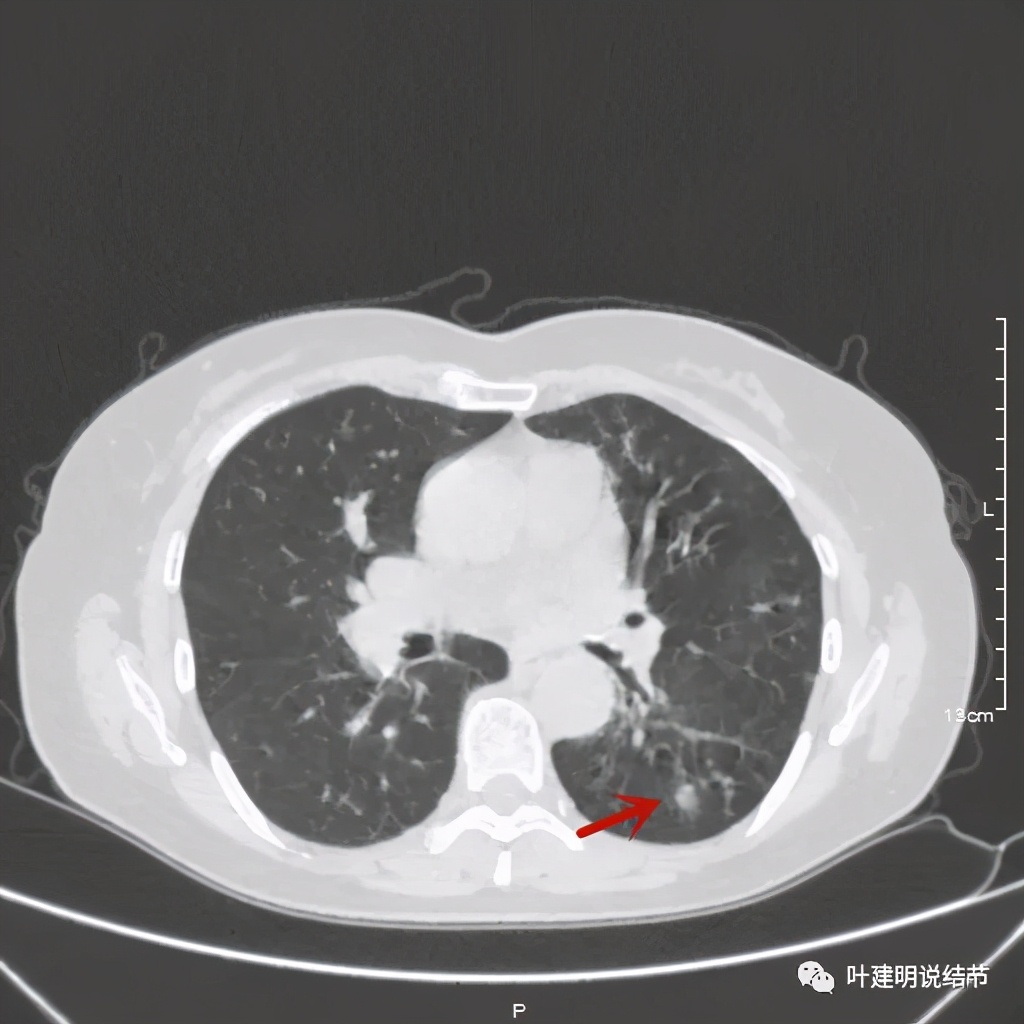

其实若从以上影像上看,恶性还真不能除外的,相对来说,恶性的可能应该大于良性。但看肺结节,我们在看细节特征的同时,还要看其他肺野有没有异常,综合来考虑。因为她的左下肺其他部位有病变存在,先来看下图像:

左下肺野多发支气管扩张呈囊状,也有一些实性密度的结节(考虑扩张支气管内的痰栓)。右侧也有实性炎性病灶。所以综合来看,左下之前的结节也得考虑与这些同源,一个原因来解释更为合理,所以恶性的可能性又小了。我建议其随访观察。昨天来复查,我们来看下这次的CT图像: